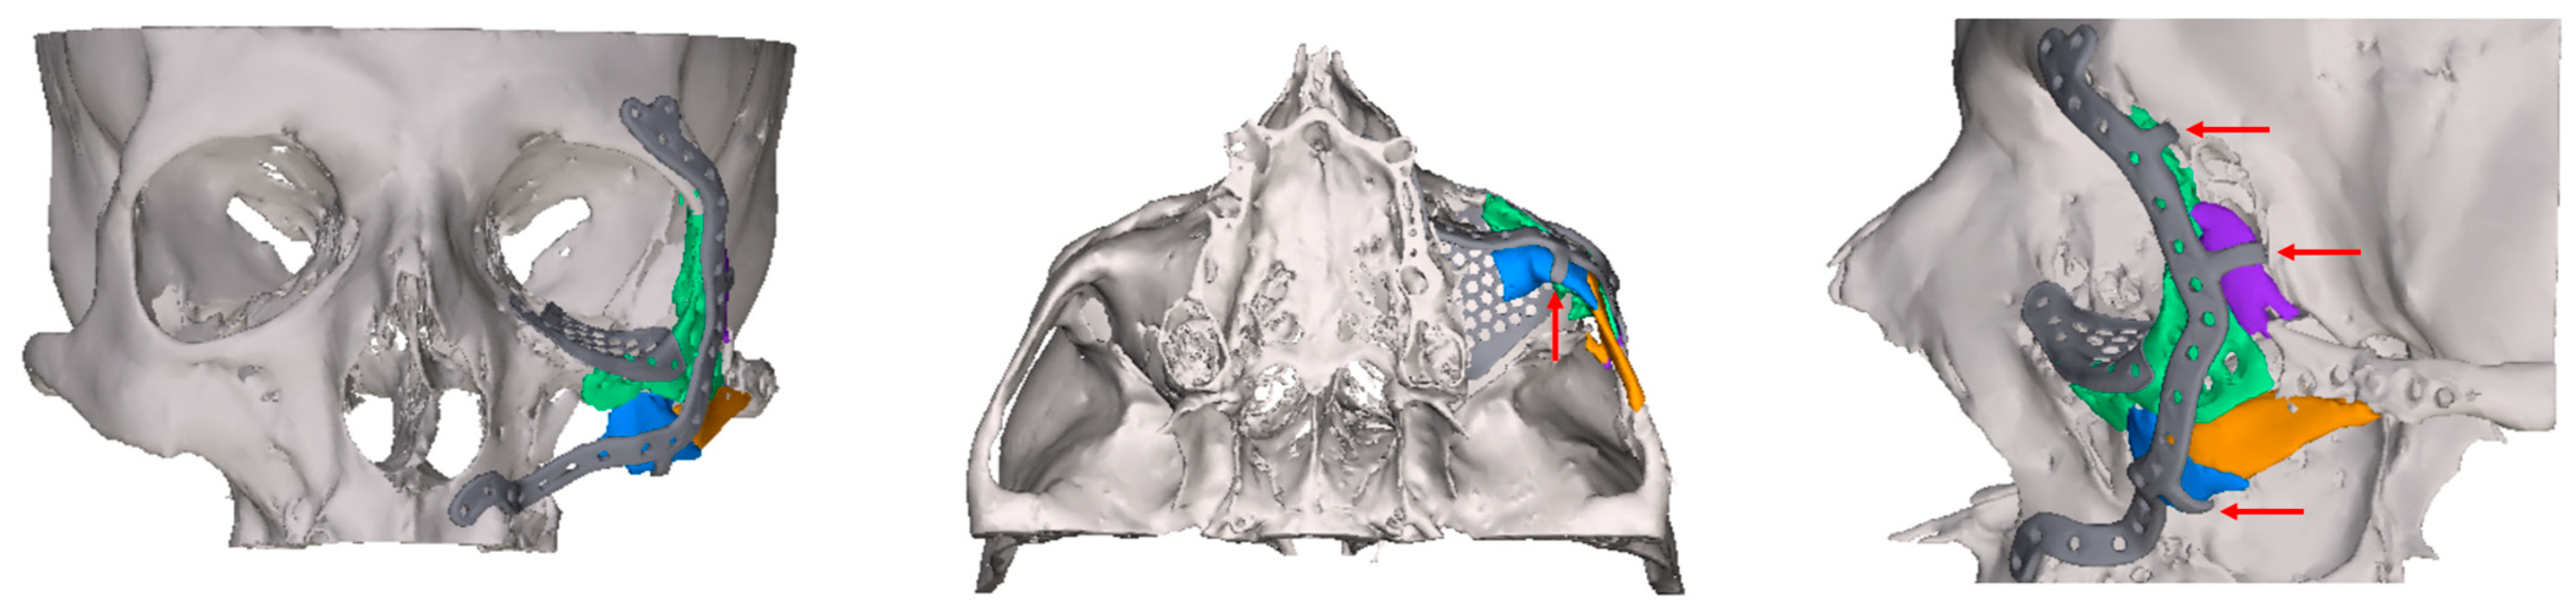

2.2. Digital Workflow and Implants

- Patent ostium of the maxillary sinus (coronal plane)

- Non-inflammatory PNSs (three planes)

- Exposure of the osteosynthesis screws (axial and sagittal planes)

- Exposure of the PSI to the maxillary sinus (coronal and sagittal planes)

- Remodeling of the fractured orbital walls and bone apposition at the PSI indicating osseointegration (three planes)

- Exposure of the fixation screws (infraorbital recess of the maxillary sinus) and limited exposure of the PSI (transition zone, ethmoid cells) without signs of mucosal swelling in these regions (n = 6 each)

- (Basal) mucosal swelling in the maxillary sinus indicative of chronic maxillary sinusitis, irrespective of the complexity of the primary injury (n = 4)

- Bone apposition at the PSI as a sign of osseointegration (n = 16)

- Remodeling of the dislocated bone fragments of the orbital walls (n = 16), including in the area of the infraorbital canal.